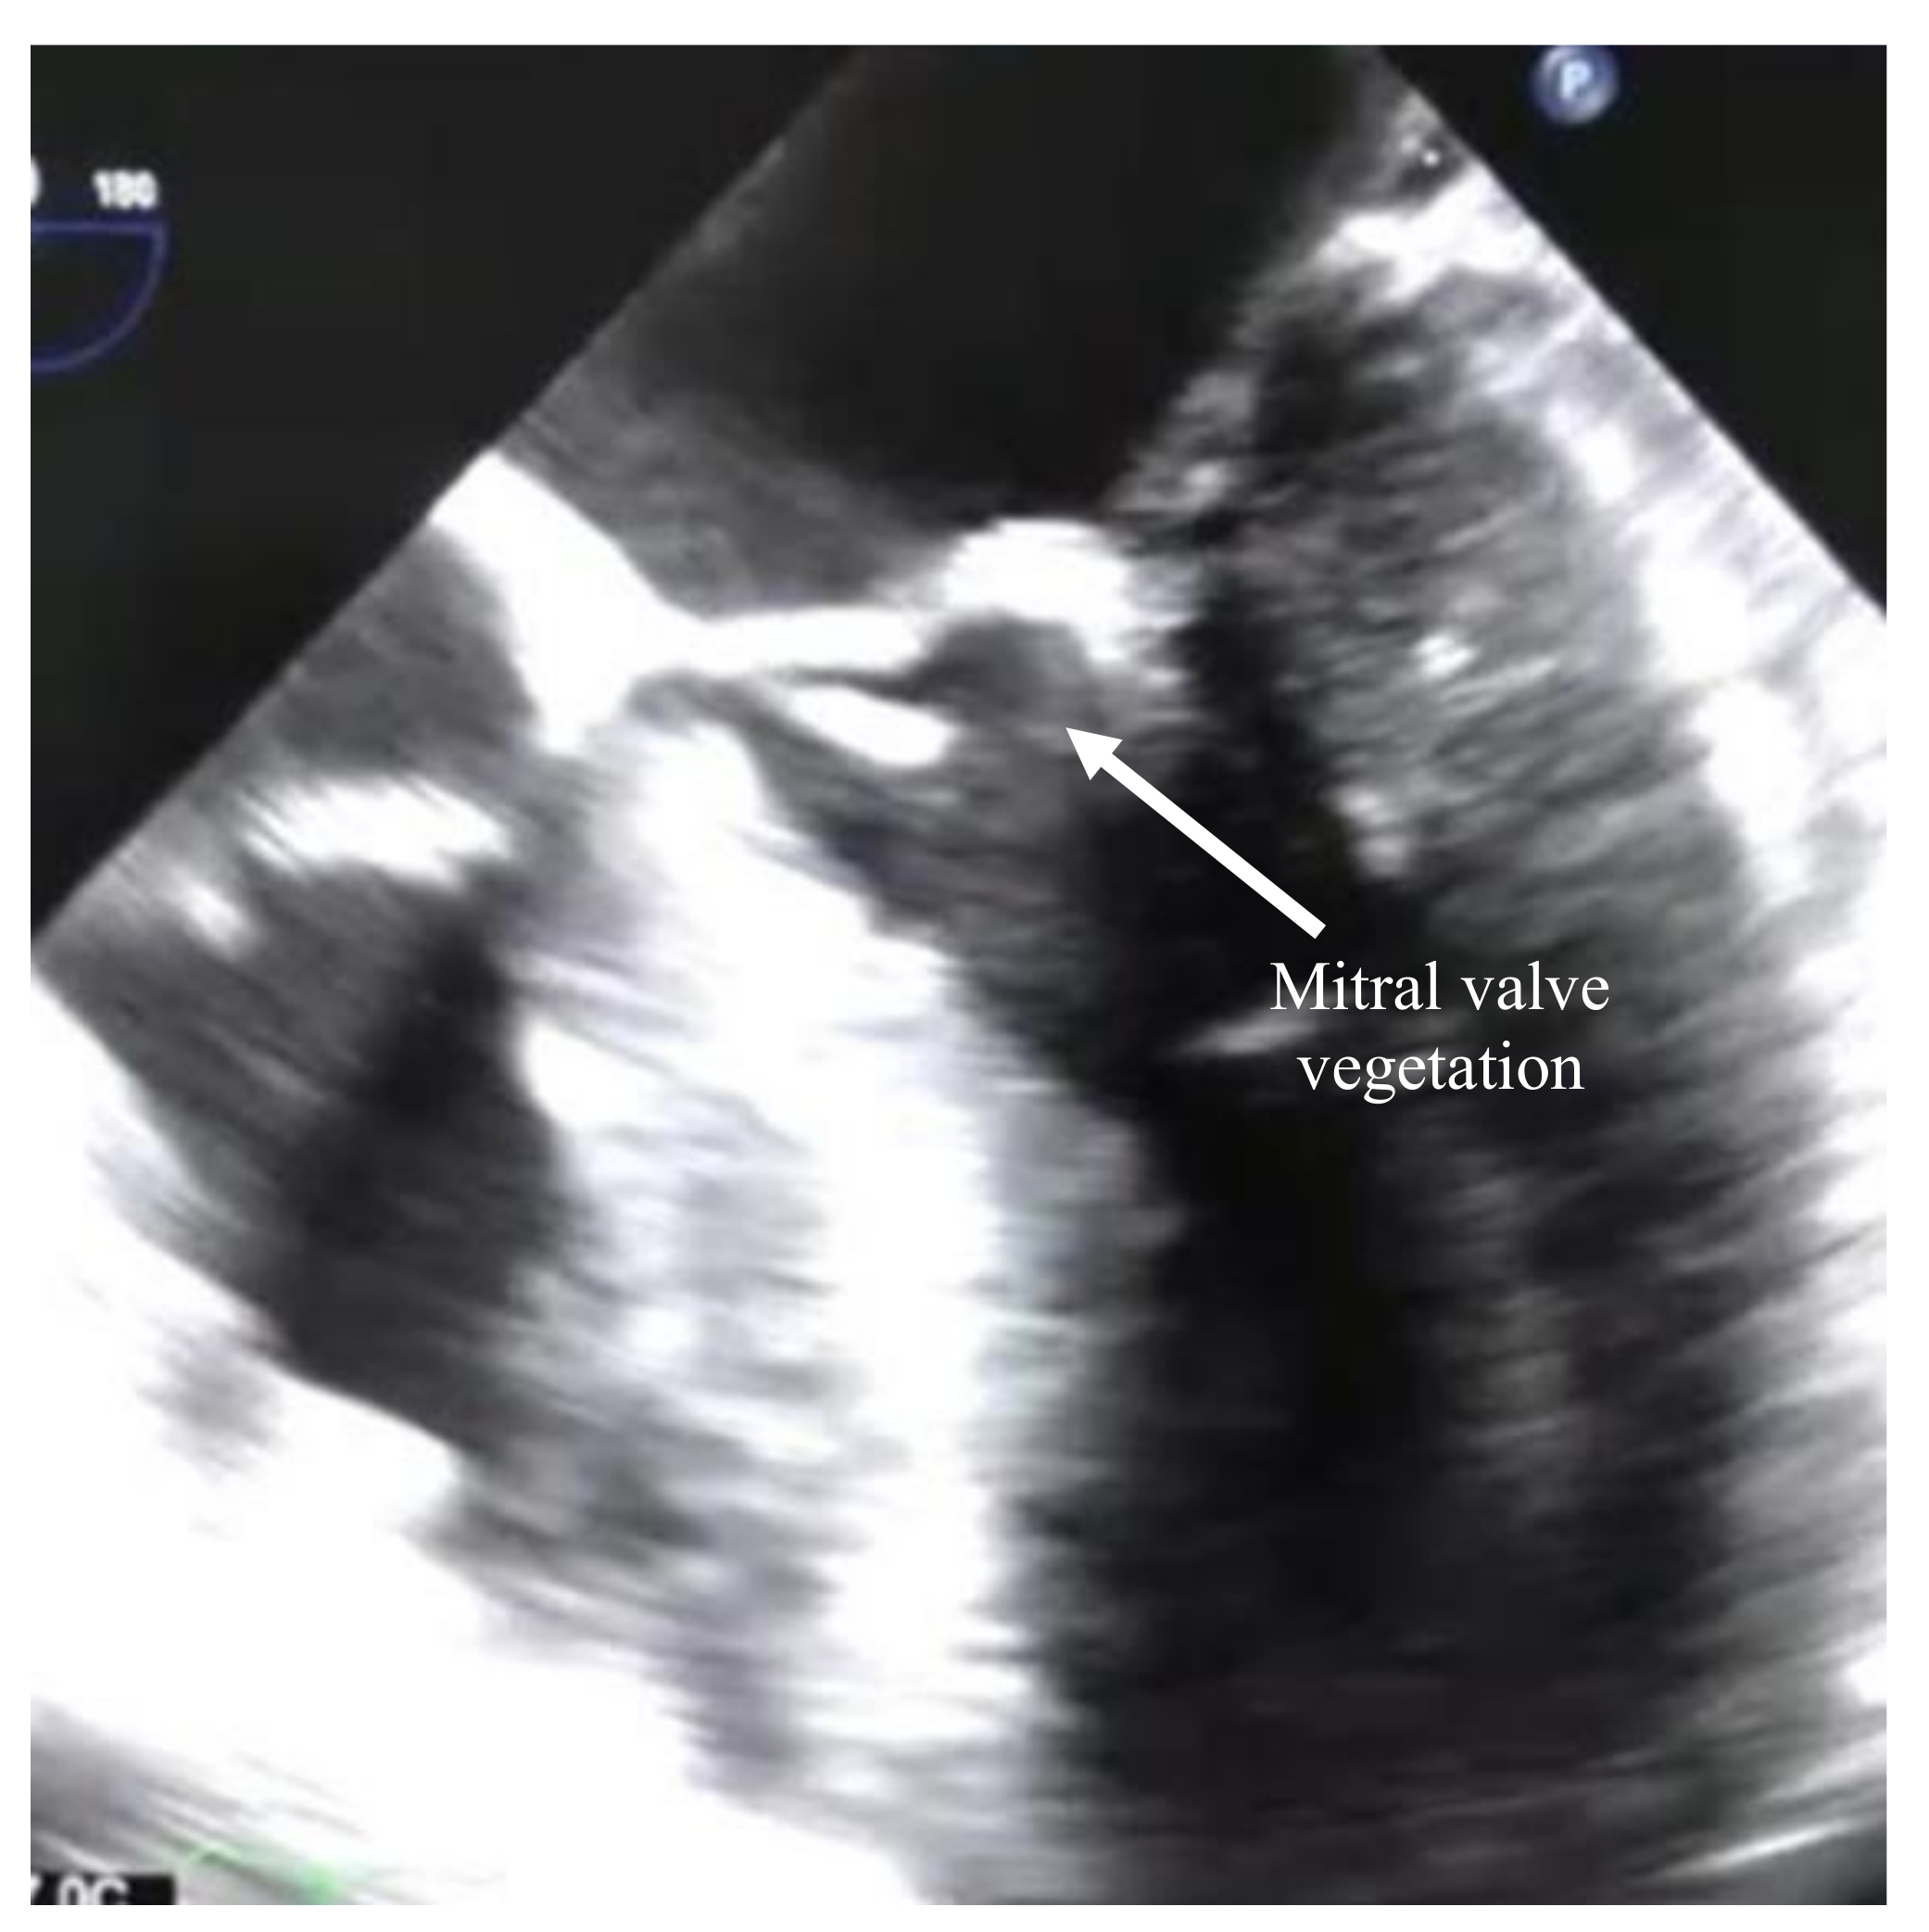

1. Case Report